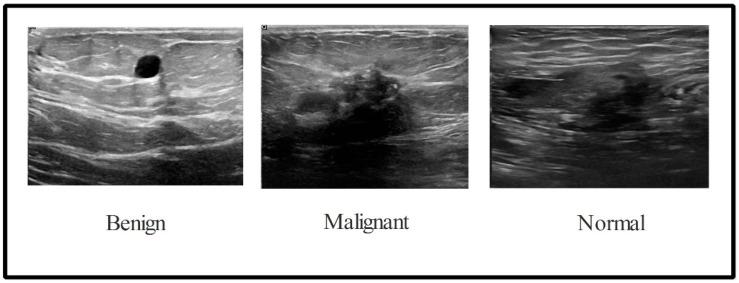

After lung cancer, breast cancer is the second leading cause of death in women. If breast cancer is detected early, mortality rates in women can be reduced. Because manual breast cancer diagnosis takes a long time, an automated system is required for early cancer detection. This paper proposes a new framework for breast cancer classification from ultrasound images that employs deep learning and the fusion of the best selected features. The proposed framework is divided into five major steps: (i) data augmentation is performed to increase the size of the original dataset for better learning of Convolutional Neural Network (CNN) models; (ii) a pre-trained DarkNet-53 model is considered and the output layer is modified based on the augmented dataset classes; (iii) the modified model is trained using transfer learning and features are extracted from the global average pooling layer; (iv) the best features are selected using two improved optimization algorithms known as reformed differential evaluation (RDE) and reformed gray wolf (RGW); and (v) the best selected features are fused using a new probability-based serial approach and classified using machine learning algorithms. The experiment was conducted on an augmented Breast Ultrasound Images (BUSI) dataset, and the best accuracy was 99.1%. When compared with recent techniques, the proposed framework outperforms them.

肺癌之后,乳腺癌是导致女性死亡的第二大主要原因。如果乳腺癌能够早期发现,女性的死亡率可以降低。由于手动乳腺癌诊断需要很长时间,因此需要一个自动化系统来进行早期癌症检测。本文提出了一种新的基于超声图像的乳腺癌分类框架,该框架采用深度学习和最佳选择特征融合。该框架分为五个主要步骤:(i)进行数据扩充,以增加原始数据集的大小,从而更好地学习卷积神经网络(CNN)模型;(ii)考虑预训练的 DarkNet-53 模型,并根据扩充数据集的类别修改输出层;(iii)使用迁移学习训练修改后的模型,并从全局平均池化层提取特征;(iv)使用两种改进的优化算法(即改进的差分评估(RDE)和改进的灰狼(RGW))选择最佳特征;(v)使用新的基于概率的串行方法融合最佳选择的特征,并使用机器学习算法进行分类。实验在扩充的乳腺超声图像(BUSI)数据集上进行,最佳准确率为 99.1%。与最近的技术相比,该框架表现出色。